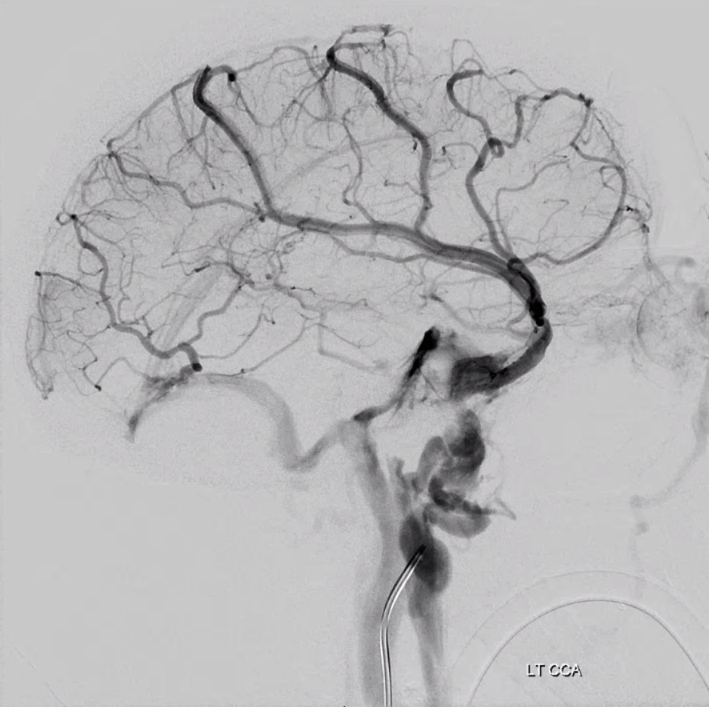

All of the above anatomic knowledge can become very useful in evaluation of venous thrombosis. Numerous collateral pathways develop in this setting attempting to compensate for the loss. The most dramatic cases usually involve the largest channel — the superior sagittal sinus. In this case, a man presented with what initially was thought to be vasculitis-related brain hemorrhage. Subsequent workup led to an angiogram, where sagittal sinus thrombosis with extensive trans-cerebral and trans-osseous emissary vein collateral channels was seen. In retrospect, these findings were present on the patient’s earlier contrast MRI. “Venovibe” or other contrast-enhanced MR venograms can very sensitive, particularly when interpreted with the appropriate index of suspicion. Noncontrast 2-D time of flight MRV I consider to be next to useless as a problem-solving technique. Any thin-slice postcontrast T1 study is vastly superior.